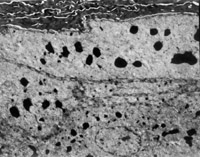

傷后12h急診入院,檢查雙下肢為淺Ⅲ度燒傷。創(chuàng)面表皮已壞死剝脫,真皮層變性壞死呈蠟黃色和蠟白色相間(圖5-3-1)。取局部組織做病理切片檢查,顯示上皮組織全層壞死,真皮層膠原纖維變性,結(jié)構(gòu)紊亂,微循環(huán)瘀滯(圖5-3-2)。

5-3-2 上皮組織全層壞死,膠原纖維變性,微循環(huán)瘀滯 HE×20